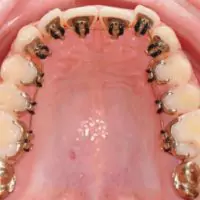

Braces

Fixed Braces

These are the braces, which are stuck onto the teeth with the help of chemicals. Broadly speaking, they are made up of steel or tooth-coloured ceramic. With the help of wire elastics, e-chains the teeth are pushed back. You might experience some discomfort and pain after the braces are placed. But with painkillers and time, patients get used to it. Fixed braces are used in cases where irregularity of teeth or malocclusion is more. Proper care should be taken in terms of brushing & cleaning of teeth regularly.

Different types of braces

steel braces

The most common and recognizable braces are the stainless steel braces. These braces are very durable and different color ties may be used with them for decorative purposes to enhance the orthodontic experience.